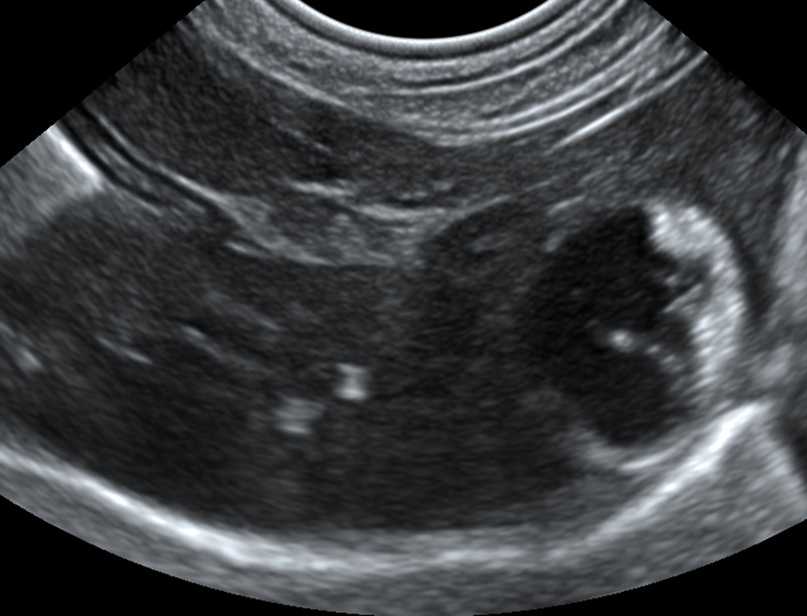

На гастроэнтерологический прием поступила собака 2 лет породы мальтийская болонка за получением 2го мнения. В анамнезе указан диагноз: патология печени и желчного пузыря. Пациент находится на терапии урсодезоксихолевой кислотой и на рационе Hepatic. Клинические жалобы отсутствуют. В желчном пузыре наблюдалась гравитационно-зависимая гиперэхогенная взвесь, занимающая до 1\3 полости [рис.1]. Так же был выполнен тест оценки объема желчного пузыря натощак и через 30 мин. Желчный пузырь практические не изменял свой объем, что свидетельствовало о сниженной сократимости и моторике желчного пузыря.

Рис.1 Ультразвуковая картина желчного пузыря при первичном обращении

На приеме была выполнена комплексная диагностика, включающая в себя общеклинический анализ крови с гемограммой, в котором обнаружен легкий левый сдвиг, признаки регенераторной анемии в виде повышения MCV и обнаружения полихроматофилов в гемограмме, биохимия крови, в которой отмечается повышение АЛТ- 343 Ед/л (норма 10-50), ГГТ 11 Ед/л (норма 0-6), щелочная фосфотаза 101 ед/л (норма 10-80) и ультразвуковая диагностика, в ходе которой обнаружена утолщенная и гиперэхогенная стенка желчного пузыря, размером 0,22 см, в просвете которого по краю стенки прикреплены параллельные гиперэхогенные тяжи, не изменяющие положение при ротации животного. Печень имеет нормальную эхогенность и размер, сосудистый рисунок выражен [рис.2].

Рис.2 Ультразвуковая картина желчного пузыря